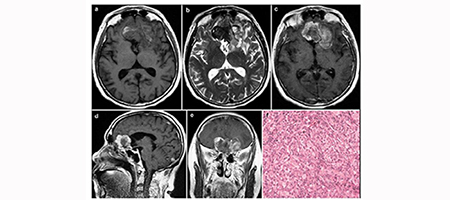

10. Clinical features and prognostic factors of primary intracranial malignant fibrous histiocytoma: A report of 8 cases and a literature review

Peng Li, Qiangyi Zhou, Zhijun Yang, Zhenmin Wang, Shiwei Li, Xingchao Wang, Bo Wang, Fu Zhao, Pinan Liu

临床转化神经科学    2016, 2 (3): 155-164.   DOI: 10.18679/CN11-6030/R.2016.024

摘要538)      PDF (2702KB)(697)

Objective: Primary intracranial malignant fibrous histiocytoma (MFH) is rare. We describe the detailed clinical features of 8 cases and fully review the literature to evaluate several prognostic factors. Methods: Eight patients with pathologically confirmed primary intracranial MFH were retrospectively reviewed. We searched PubMed for relevant articles with the term "intracranial malignant fibrous histiocytoma". Results: Of the 8 patients, 4 were men and 4 were women. Three patients had received previous radiotherapy. The age of the patients ranged from 19 to 69 years, with a median age of 48 years. Most tumors could be totally resected; and only 1 tumor was subtotally resected. Six patients received postoperative radiotherapy and 3 patients received postoperative chemotherapy. Most patients died within the first year after surgery; and only 1 patient was still alive on the date of the last follow-up. We reviewed the literature and included a total of 46 patients in the Kaplan-Meier survival analysis. Young patients (less than 30 years old) seemed to have a better prognosis and survival rate than older patients (more than 30 years old) (log-rank test, P=0.008). However, sex (P=0.675), extent of resection (P=0.934), postoperative radiotherapy (P=0.592), and postoperative chemotherapy (P=0.424) did not affect patient prognosis. Conclusions: The prognosis of MFH is usually poor, and most patients die within the first year after surgery. Younger MFH patients (less than 30 years old) seem to have a better prognosis and improved survival compared to older patients.

图表 | 参考文献 | 相关文章 | 多维度评价